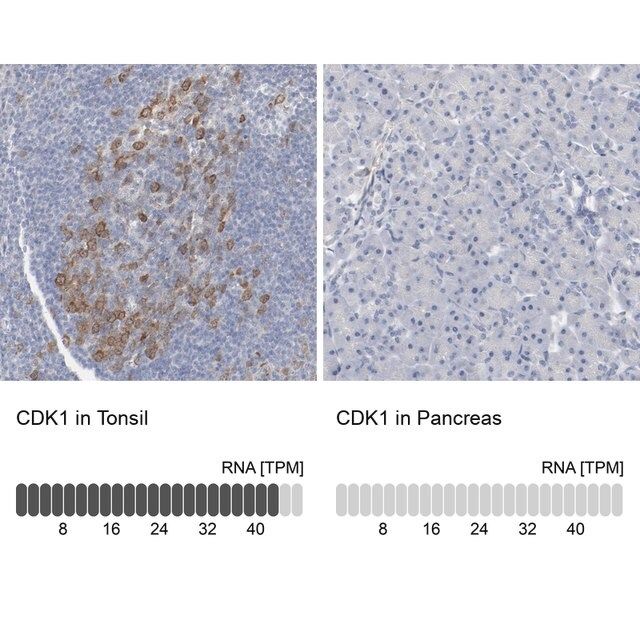

Anti-CDK1 antibody produced in rabbit, a Prestige Antibody, is developed and validated by the Human Protein Atlas (HPA) project (www.proteinatlas.org). Each antibody is tested by immunohistochemistry against hundreds of normal and disease tissues. These images can be viewed on the Human Protein Atlas (HPA) site by clicking on the Image Gallery link. The antibodies are also tested using immunofluorescence and western blotting. To view these protocols and other useful information about Prestige Antibodies and the HPA, visit sigma.com/prestige.

- IHC tissue array of 44 normal human tissues and 20 of the most common cancer type tissues.